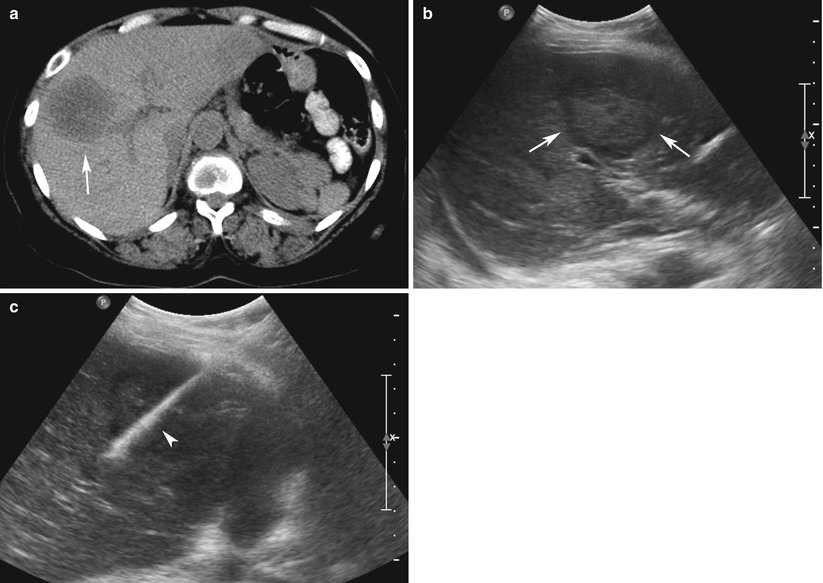

An ultrasonographyguided biopsy of the liver. A suspected metastasis... Download HighQuality Liver Biopsy Procedure Ultrasound They will insert the needle through. a liver biopsy is a minor procedure to take a tiny tissue sample from your liver through a hollow needle. all patients who need liver biopsy should ideally have had an ultrasound before the. a liver biopsy is a procedure to remove a small piece of liver tissue, so it can. Liver Biopsy Procedure Ultrasound.